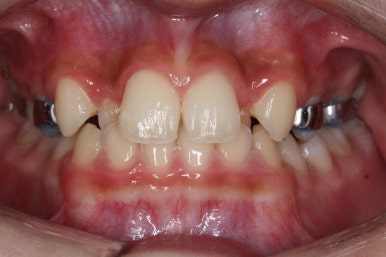

이 후에 장치를 부착하여 치아를 가지런하게 해주기 시작합니다.

키달이저씨치과에서 사용한 장치는 메탈 자가결찰 장치인 엠파워 메탈 장치를 사용했습니다. 메탈장치는 굉장히 장점이 많은 장치입니다.

장치 부착 직후의 얼굴 모습입니다.

부피가 그리 크지 않은 장치이기 때문에, 교정장치를 부착하였다고 해서 입이 많이 튀어나오거나 하지는 않습니다. 대신 웃을 때 눈에 확 드러나 보이기는 합니다.